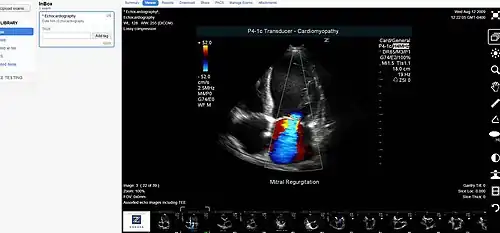

Medical image sharing is the electronic exchange of medical images between hospitals, physicians and patients. Rather than using traditional media, such as a CD or DVD, and either shipping it out or having patients carry it with them, technology now allows for the sharing of these images using the cloud. The primary format for images is DICOM (Digital Imaging and Communications in Medicine). Typically, non-image data such as reports may be attached in standard formats like PDF (Portable Document Format) during the sending process. Additionally, there are standards in the industry, such as IHE Cross Enterprise Document Sharing for Imaging (XDS-I), for managing the sharing of documents between healthcare enterprises. A typical architecture involved in setup is a locally installed server, which sits behind the firewall, allowing secure transmissions with outside facilities. In 2009, the Radiological Society of North America launched the "Image Share" project, with the goal of giving patients control of their imaging histories (reports and images) by allowing them to manage these records as they would online banking or shopping.[1]

- Picture archiving and communication system (PACS) - A medical imaging technology that provides economical storage of, and convenient access to, images from multiple modalities within a facility.

- DICOM - A standard for handling, storing, printing, and transmitting information in medical imaging.